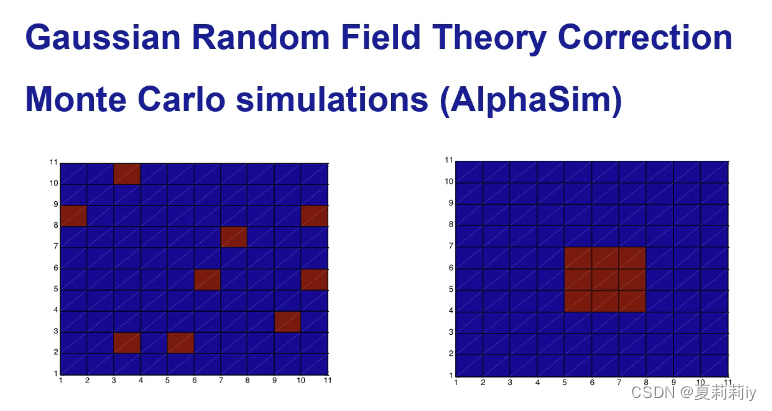

④Gaussian Random Field Theory Correction(GRF Correction)

⑤AlphaSim Correction:不是很推荐